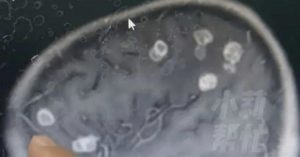

2018年10月,袁惟仁在上海意外跌倒,头部重创引发脑溢血,紧急送医后又被发现脑内有良性肿瘤,历经长时间手术与抢救后,一度脱离险境,返台休养。